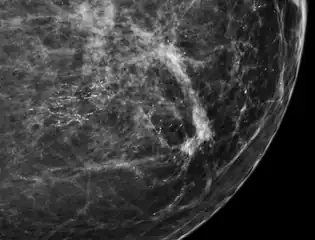

Mammogram microcalcifications in ductal carcinoma in situ

Microcalcifications are tiny deposits of calcium salts that are too small to be felt but can be detected by imaging.[1]

They can be scattered throughout the mammary gland, or occur in clusters. Microcalcifications can be an early sign of breast cancer. Based on morphology, it is possible to classify by radiography how likely microcalcifications are to indicate cancer. [2]

In contrast to an artifact of crowded cells, the DCIS calcification pictured above characteristically extends outside the focal plane, as the background DCIS is blurred in this focus.